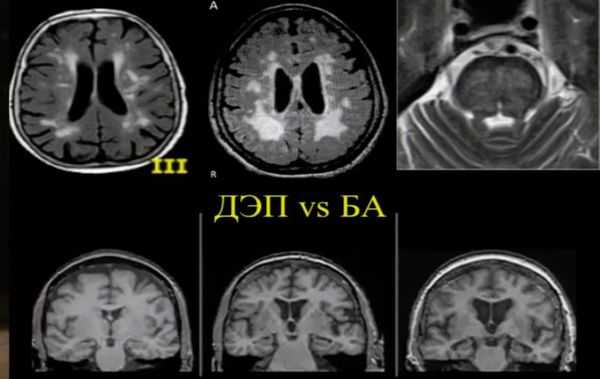

МРТ и КТ головного мозга

Современные методы нейровизуализации — магнито-резонансная томография и компьютерная томография головного мозга — позволяют расширить диагностические возможности прижизненной диагностики болезни Альцгеймера.

МРТ и КТ проводят для выявления поддающихся лечению причин деменции и нарушений, которые могут усугубить симптомы. Структурные изменения по данным магнитно-резонансной томографии являются более прогностически значимыми для дальнейших изменений в когнитивной сфере, чем биомаркеры цереброспинальной жидкости. По данным магнитно-резонансной томографии, признаки цереброваскулярного заболевания, такие как лейкоареоз и множественные подкорковые лакунарные инфаркты, чаще наблюдаются у пациентов с болезнью Альцгеймера, чем в контрольной группе. [7] Асимметричная атрофия медиальных отделов височной доли также не исключает сосудистую деменцию.

Описана смешанная модель патогенеза болезни Альцгеймера, которая предполагает взаимодействие церебральной амилоидной ангиопатии с сосудистыми факторами на ранних стадиях патологического процесса. Предполагается, что синергия между накоплением амилоида и цереброваскулярной патологией может инициировать дальнейшую дисфункцию нейронов и нейродегенерацию. [8] В этом отношении церебральные микрокровоизлияния, выявляемые в режиме Т2 градиентного эхо на магнитно-резонансной томографии, являются дополнительным и доступным диагностическим маркером, повышающим диагностическую значимость лейкоареоза и свидетельствующим в пользу церебральной амилоидной ангиопатии или гипертонической микроангиопатиии, особенно в случаях смешанной патологии и тяжелого когнитивного дефицита.

Локализация церебральных микрокровоизлияний является дифференциально-диагностическим признаком ведущего патологического процесса. В случае болезни Альцгеймера наблюдается корковая локализация микрокровоизлияний, в случае дисциркуляторной энцефалопатии или сосудистой деменции будут визуализироваться микрокровоизлияния в глубинных отделах мозга. [9] [10]